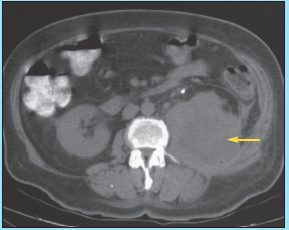

An ultrasonogram of the abdomen discloses a large hypodensity in the right lobe of the liver. The abdominal CT scan is shown here.

The abdominal CT scan shows a large, welldemarcated, hypodense lesion in the right lobe of the liver, consistent with an abscess. Features that strongly suggest pyogenic liver abscess, B, include high fever, progressive upper right quadrant pain, an enlarged liver, and a large hypoechoic lesion on ultrasonograms and CT scans.